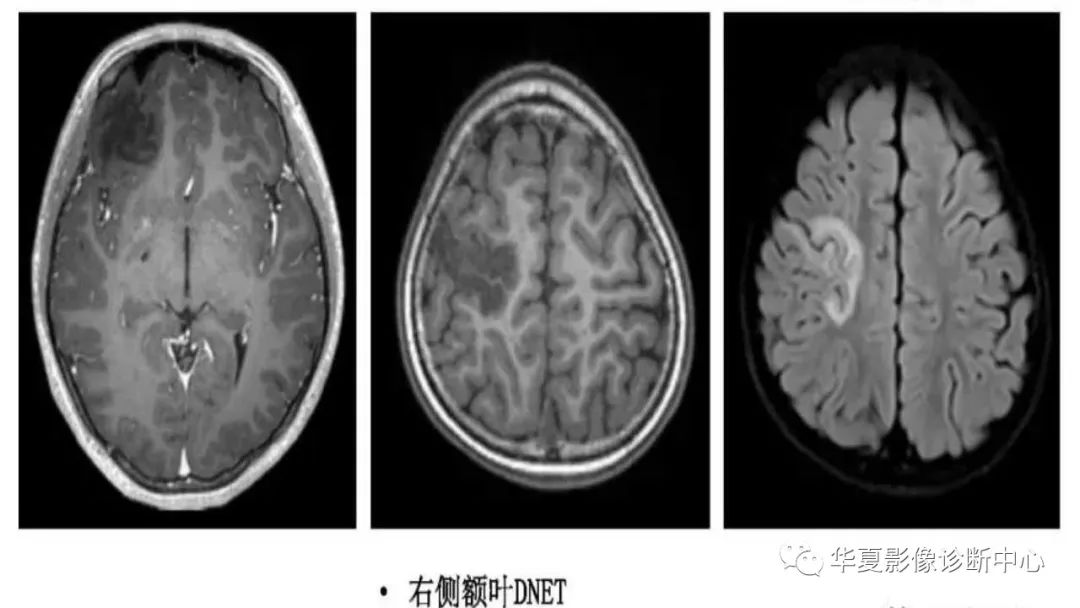

MOGHE的MRI诊断与鉴别诊断-4